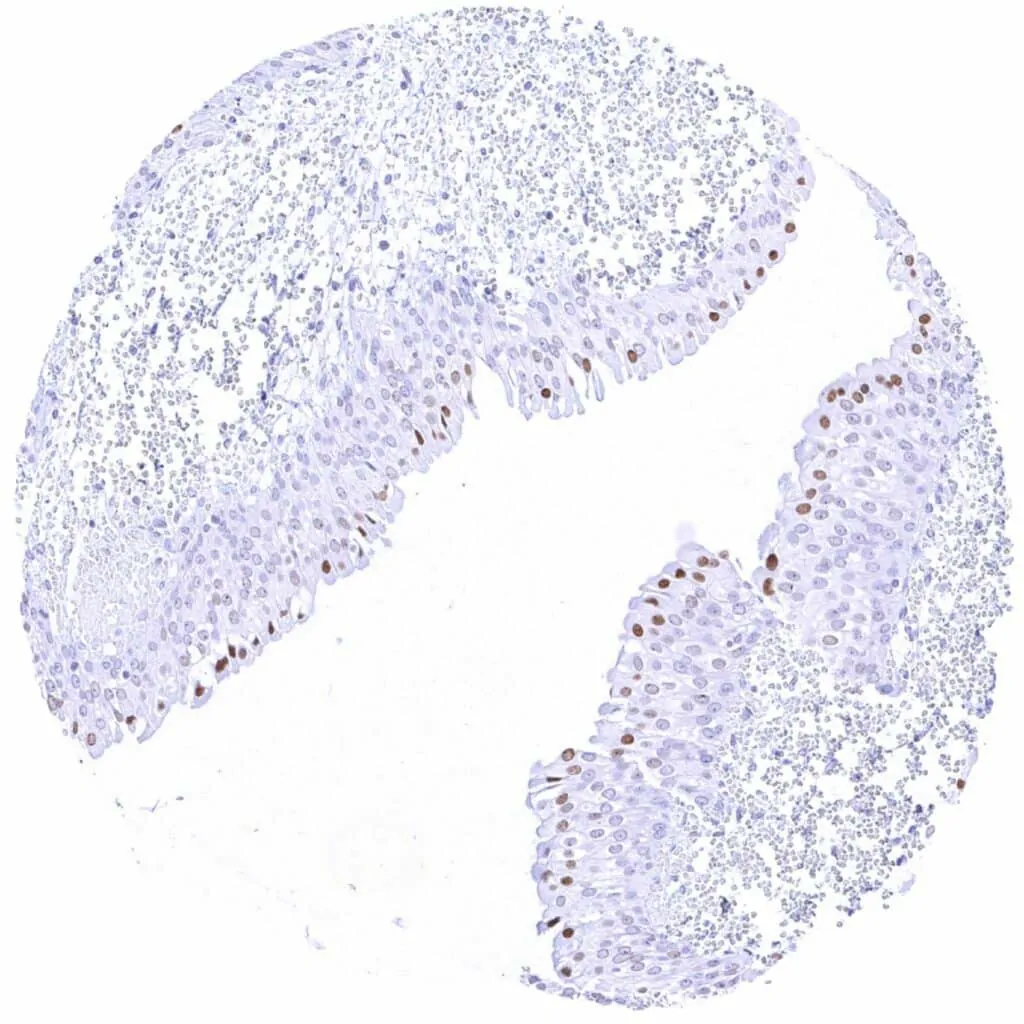

Esophagus, squamous epithelium Weak to strong nuclear Cyclin E1 staining of squamous epithelial cells in the upper half of the surface epithelium. The staining intensity gradually increases towards the surface